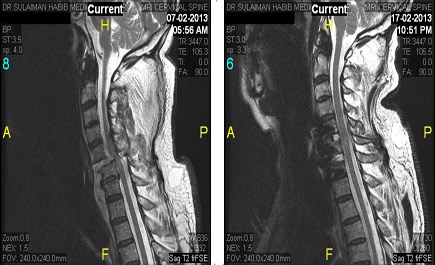

أنقذ الفريق الطبي التابع لمجموعة الدكتور سليمان الحبيب بالمجمع الطبي بالعليا حياة رجلين في العقد السابع من عمرهما إثر تعرضهما لحادث سير مروع أصيبا على أثره بعدة كسور، أدت الى فقدانهما القدرة على الحركة وضعف شديد في اليدين والقدمين حيث تم استقبالهما بقسم الطوارئ وتشخيص حالتهما عن طريق التصوير بالأشعة المقطعية (CT.scan) والرنين المغناطيسي(MRI)، وأظهرت النتائج وجود كدمات في النخاع الشوكي مما استدعى التدخل الجراحي على الفور لإنقاذ حياتهما.

وأوضح الدكتور النبهان أن العملية استغرقت ساعتين تم خلالها استئصال الغضروف المتهالك واستبداله بالغضروف الصناعي وتثبيت الفقرات ووضع دعامات بين الفقرات عن طريق الميكروسكوب.